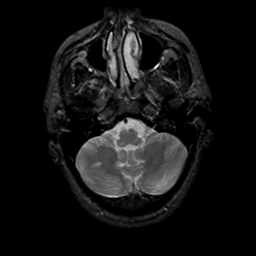

MR Study #20 October 6, 1991 -- Slice #9

[Home][Help][Clinical][Tour 1][Tour 2] Slice 9